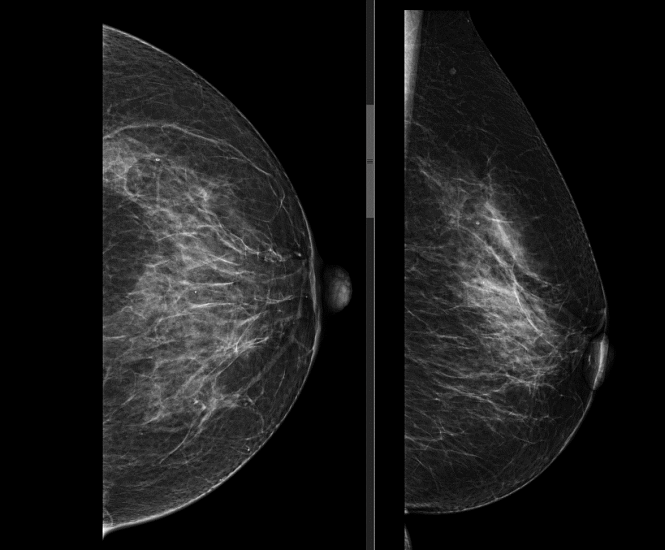

Исследование проводится стоя, предварительно сняв верхнюю и нижнюю одежду области исследования, а также все украшения в области зоны интереса. Для получения четких и подробных снимков, молочную железу располагают между двух пластин маммографа, которые слегка сдавливая, фиксируют ее в неподвижном положении, добиваясь равномерного распределения тканей. Затем специалист делает снимок молочной железы в боковой и прямой проекции. Исследуются поочередно обе груди.